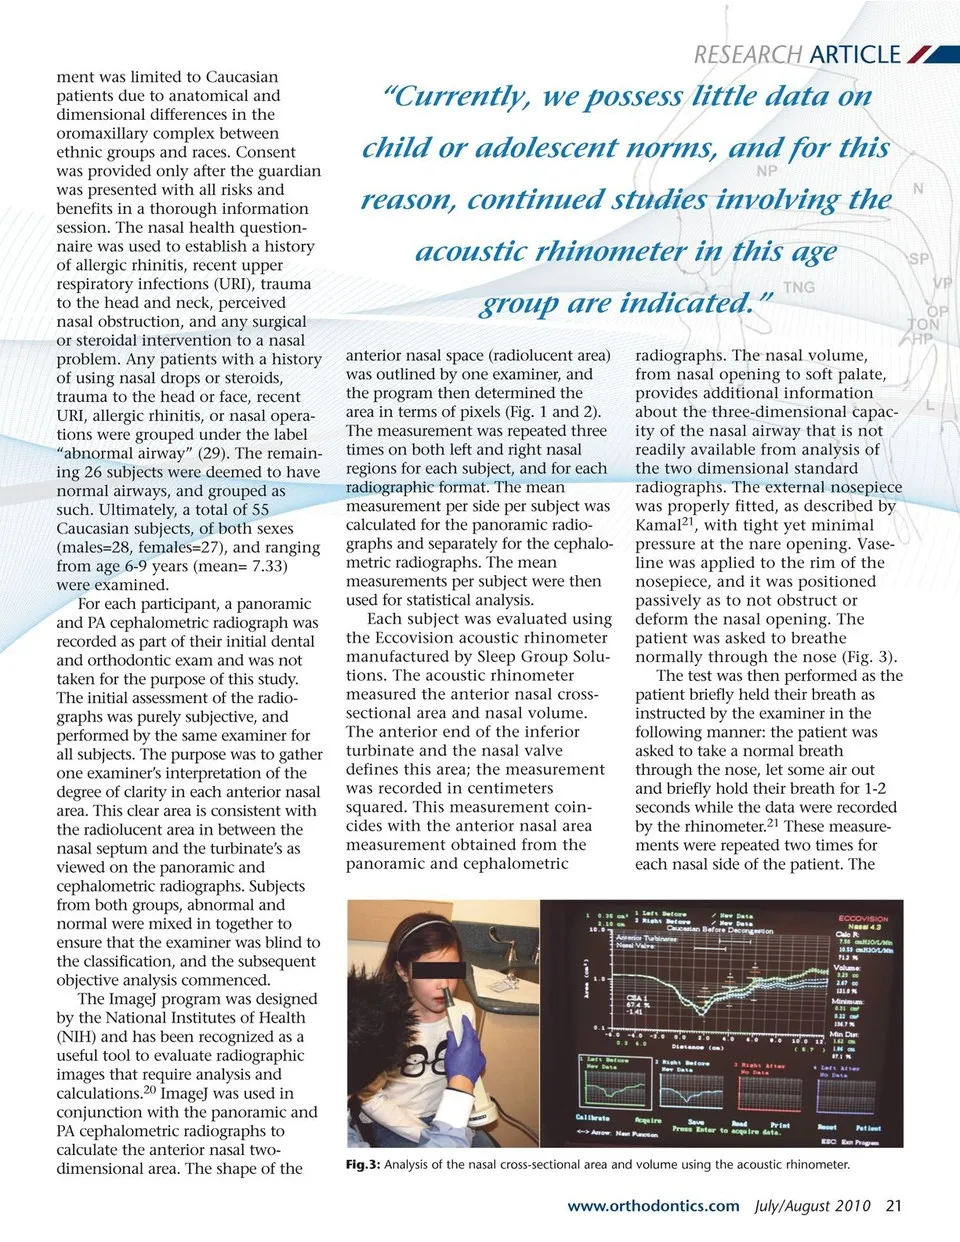

RESEARCH ARTICLE graphic images that are taken during the diag-nostic process, we can bring a better level of care to all children. By augmenting the details of the referral, the Fig.1: Sample of an Image-J tracing of the anterior nasal cross-sectional area as viewed on a panoramic radiograph. late statistics, such as area and pixel value, from uploaded images.20 Through the use of the acoustic rhinometer and the standard radio-dentist can stimu-late cooperation with the otolaryn-gologist and thus affect their will-ingness to work together on the patient’s dental treatment. The combination of information gath-ered from the assessment of the radiographs and the added informa-tion from the acoustic rhinometer results in a more thorough treat-ment plan that accounts for the airway as a significant influence. The use of acoustic rhinometry as an adjunct to radiographic examina-tion will provide an objective and non-invasive method to assess the nasal volumetric dimensions. The technique is easy to understand and is not imposing on practitioners or patients. The cross-sectional area and volume of the nasal cavity can be assessed using the acoustic reflec-tions from sound waves emitted from the rhinometer. The computer-generated graph of nasal area versus nasal cavity distance plots waves, which correspond to particular anatomical landmarks of the nasal cavity.21 Prior confirmation of the accuracy of these anatomical mark-ers has been confirmed through CT investigations.12, 22 The previous studies have provided us with adult norms that can be used for compari-son with the readings gathered from the acoustic rhinometer and a deter-mination can be made as to the patency of the airway. Currently, we possess little data on child or adoles-cent norms, and for this reason, continued studies involving the acoustic rhinometer in this age group are indicated. The need for a definitive and non-invasive evaluation tool conventional to the dental exam can be fulfilled by the acoustic rhinometer. This comprehensive evaluation method will be instru-mental in making multidisciplinary intervention to correct craniofacial abnormalities and nasal airway obstruction. The purpose of this project is to confirm the nasal airway patency observed in stan-dard dental radiographs by analyz-ing the anterior nasal cross-sectional area and nasal volume derived from acoustic rhinometry. Determining the airway status of the patient can better aid in the diagnosis and treatment planning of a dental or orthodontic case. Fig.2: Sample of an Image-J tracing of the anterior nasal cross-sectional area as viewed on a PA cephalometric radiograph. 20 July/August 2010 JAOS Materials and Methods The study was conducted at Tufts University School of Dental Medicine in the Department of Pedi-atric Dentistry. The subject recruit-